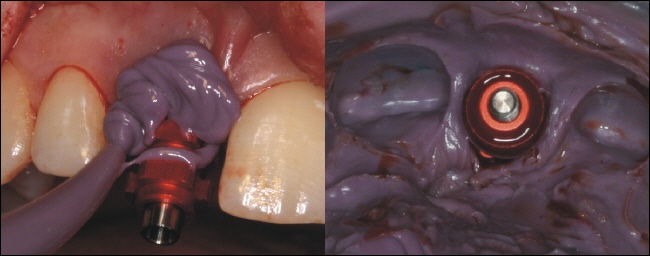

Abformung

Mithilfe einer Abformmasse wird die Implantatposition abgeformt. Das rechte Bild zeigt den zuvor auf dem Implantat montierten Pfosten nun in der aus dem Mund genommenen Abformung. Diese dient zu Herstellung eines Gipsmodells, welches die genaue Mundsituation wiedergibt. Der Zahntechniker fertigt nun auf dem Gipsmodell eine provisorische Krone an.